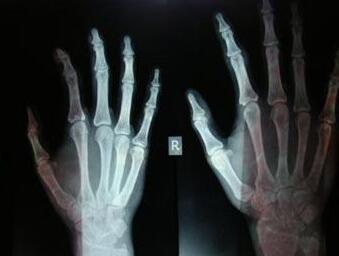

(图:王女士在医院拍的CT影像图)

杜爱华主任看到王女士全身严重浮肿,面部严重潮红,四肢关节严重变形歪斜,并且右手肘关节骨质变形增生成竹笋状骨刺。杜爱华主任通过从王女士的病情看来初步确诊为类风湿性关节炎。由于王女士全身大小关节都受到了或多或少的影响,杜爱华主任立即给王女士做了全面检查,清晰有力的判断出王女士确实是类风湿性关节炎。最后为王女士制定了相应的治疗计划。

接受两个疗程的治疗后,病情得到控制,有较明显好转。又经过1个疗程的治疗后,患者生活可完全自理,手指由变形歪斜不能自理到伸缩自如,全身浮肿完全消失,面部由严重潮红到白里透红,右手肘关节处严重变形增生的2寸长骨刺完全自然消失。复诊检查出各项指标达到临床标准。